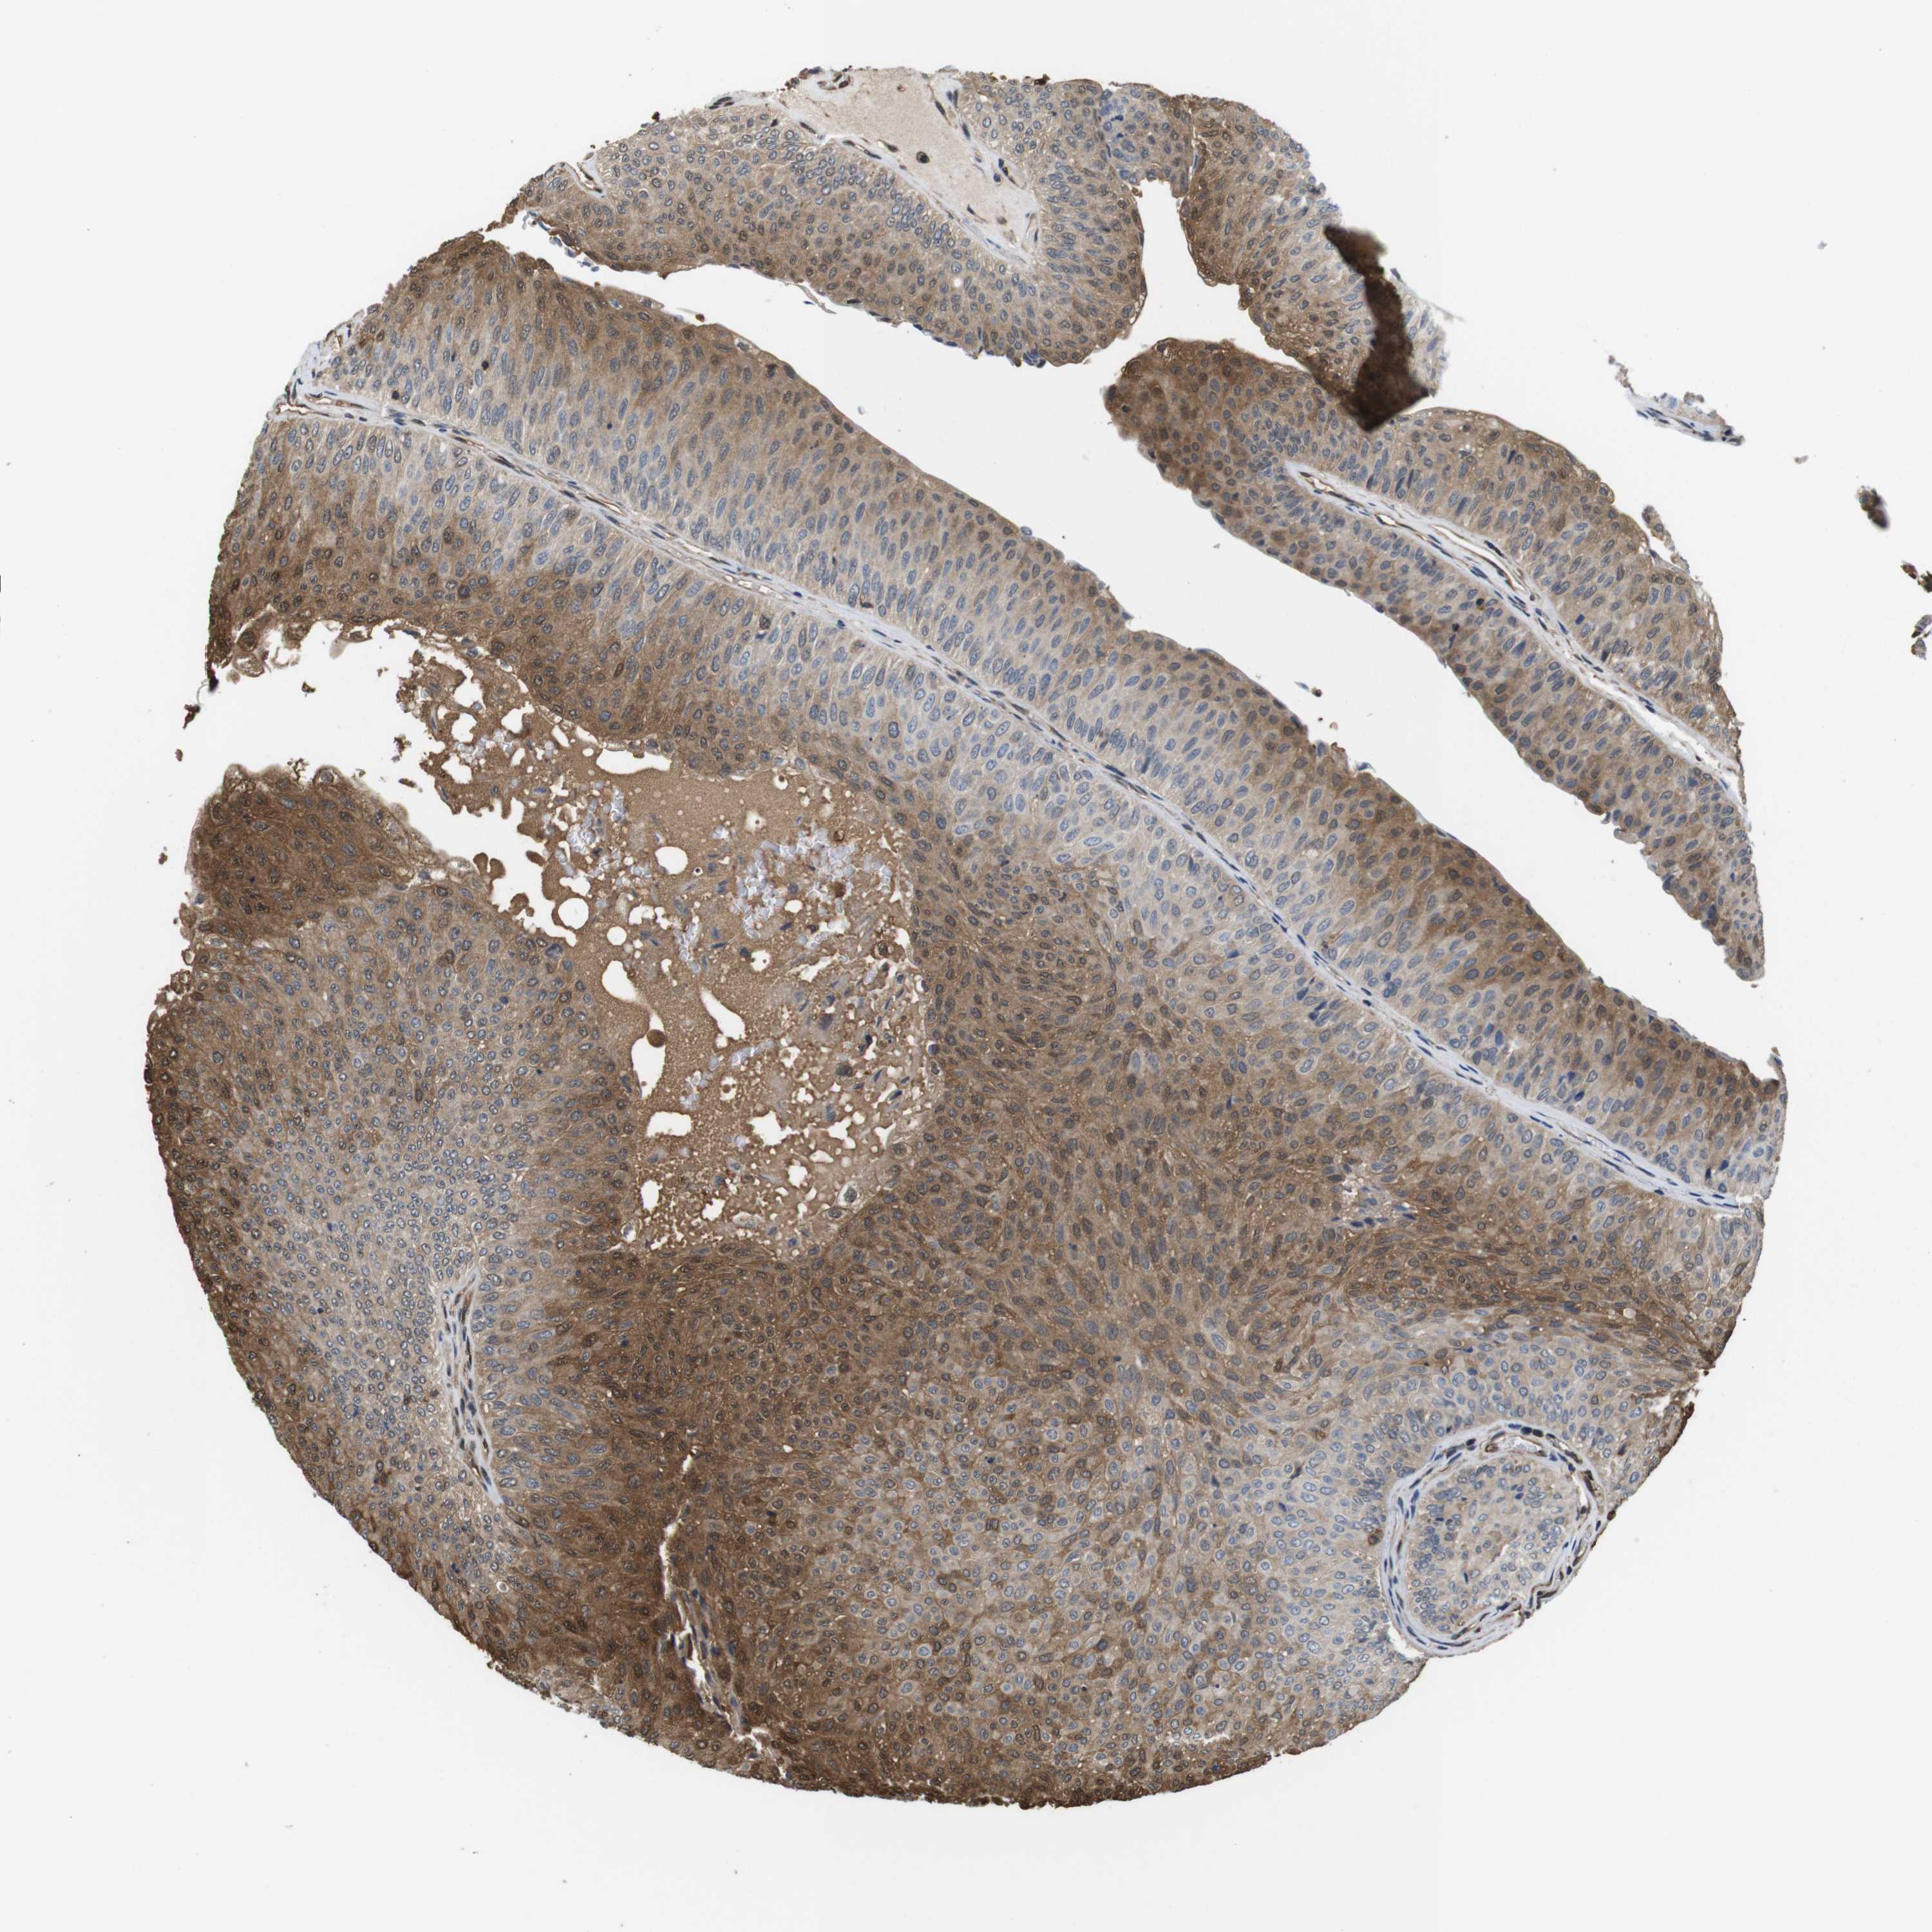

UROTHELIAL CANCER - Protein expressioni

A mouse-over function shows sample information and annotation data. Click on an image to view it in a full screen mode. Samples can be filtered based on level of antibody staining by selecting one or several of the following categories: high, medium, low and not detected. The assay and annotation is described here.

Note that samples used for immunohistochemistry by the Human Protein Atlas do not correspond to samples in the TCGA dataset.

Antibody stainingi

Antibody staining in the annotated cell types in the current human tissue is reported as not detected, low, medium, or high, based on conventional immunohistochemistry profiling in selected tissues. This score is based on the combination of the staining intensity and fraction of stained cells.

Each image is clickable and will lead to virtual microscopy that enables deeper exploration of all samples and also displays staining intensity scores, fraction scores and subcellular localization as well as patient and tissue information for each sample.

Antibody CAB015336

Antibody CAB069404

Staining

High

Medium

Low

Not detected

Intensity

Strong

Moderate

Weak

Negative

Quantity

>75%

75%-25%

<25%

None

Location

Nuclear

Cytoplasmic/membranous

Cytoplasmic/membranous,nuclear

Urothelial carcinoma, Low grade

Urothelial carcinoma, High grade

Urothelial carcinoma, NOS